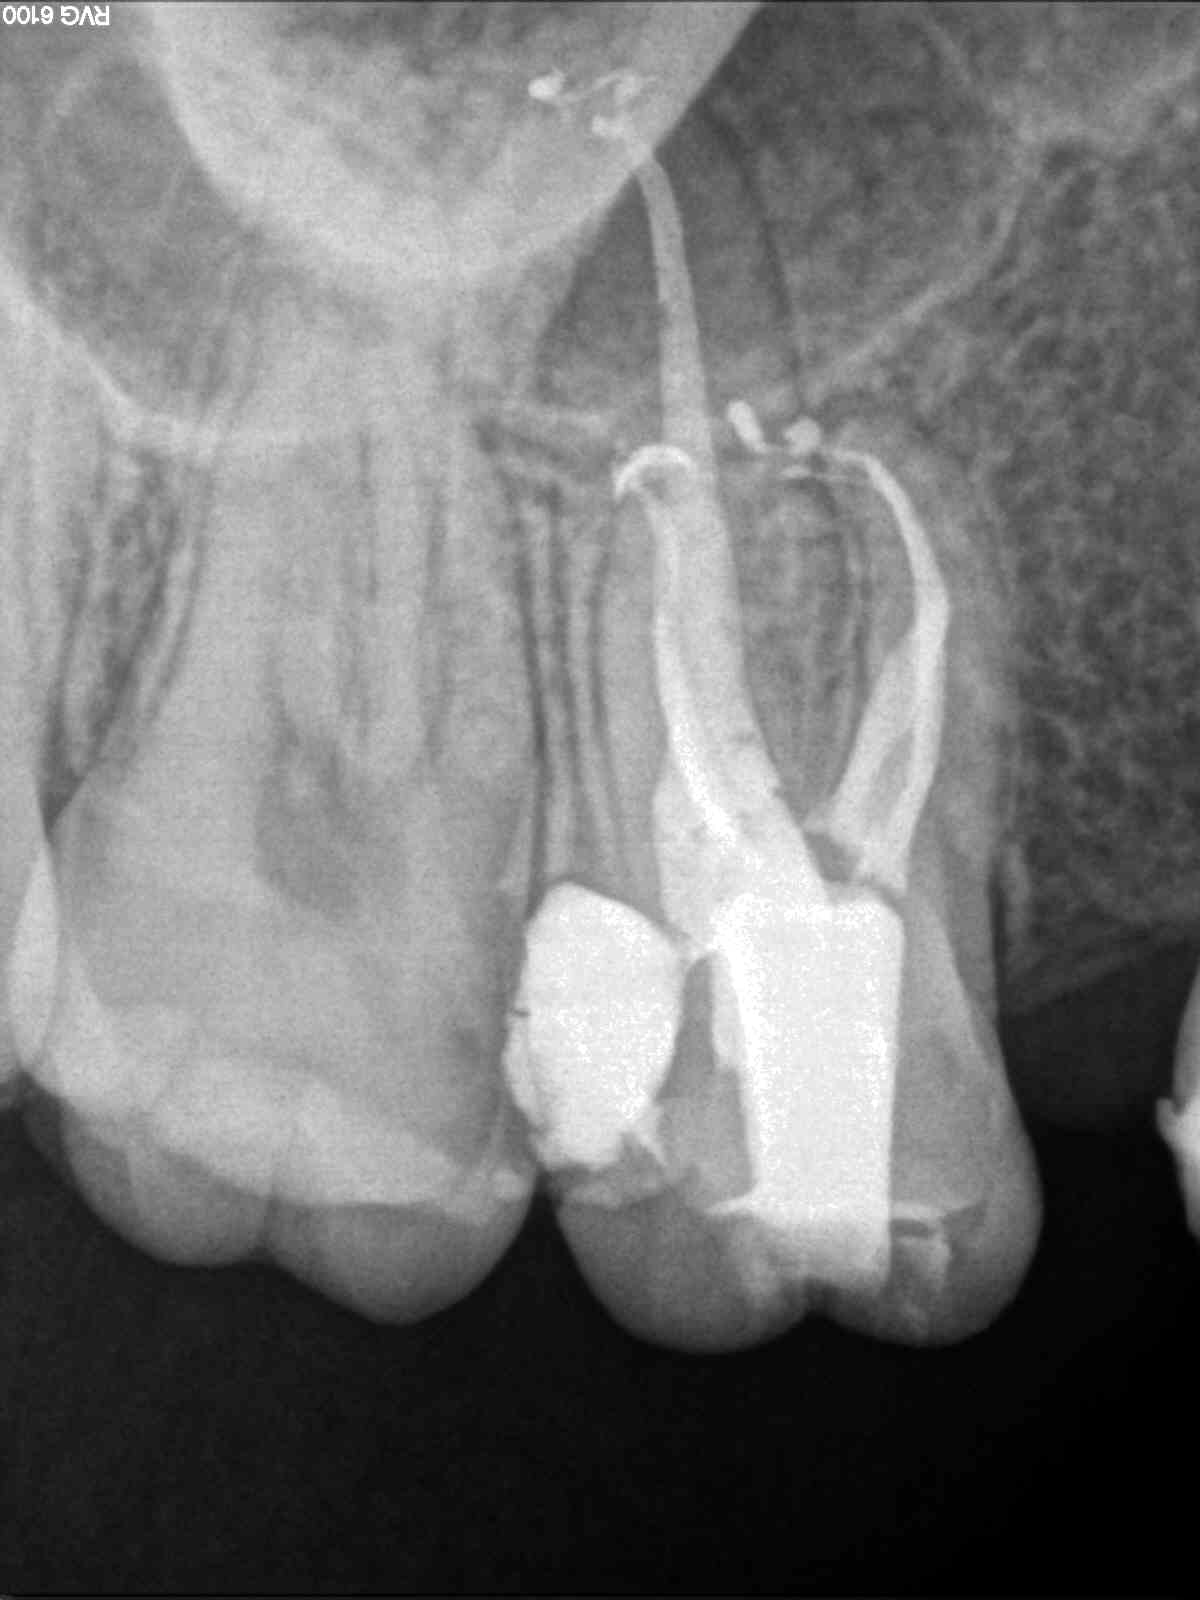

A)  Nos encontramos con un 1.7, con una necrosis pulpar con afectación periapical.

A)